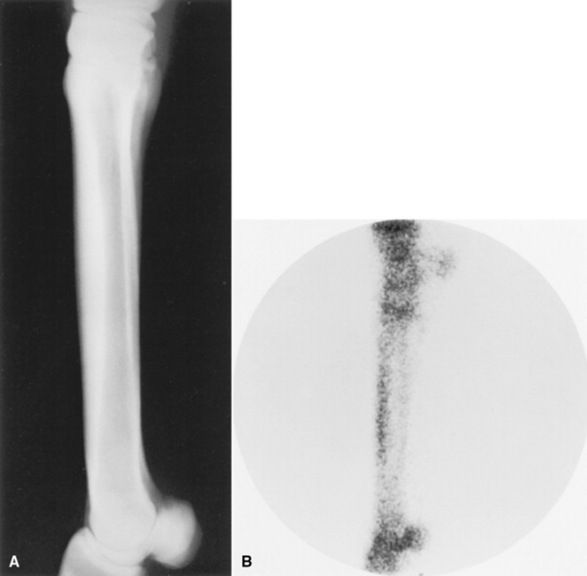

Incomplete cortical fractures may be detected radiographically; however, not all fractures can be visualized. Fracture lines usually extend in a proximopalmar direction from the periosteal surface of the dorsal cortex at a 30- to 45-degree angle to the dorsal cortical surface (Fig. 38-44, A). Occasionally, fractures extend in a distopalmar direction from the periosteal surface, and less frequently a saucer-shaped fragment is noted within the dorsal cortex. Fractures rarely appear to course completely to the endosteal surface of the dorsal cortex. In the absence of a radiolucent fracture line, a localized periosteal or endosteal reaction is highly indicative of an incomplete cortical fracture. Alternatively, occult fractures may be identified with bone scintigraphy by intense focal accumulation of radiopharmaceutical414 (Fig. 38-44, B).

image

Fig. 38-44 A, Lateromedial radiograph, and B, lateral scintigram, of the third metacarpal bone of a horse with an incomplete cortical fracture (arrow) associated with focal, intense radiopharmaceutical uptake.

Courtesy P.D. Koblik.